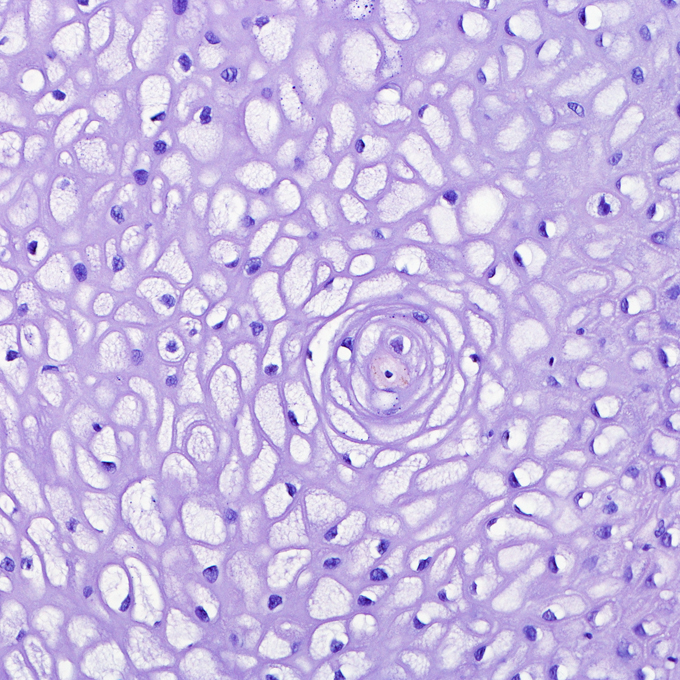

Routinehistologie

Die Routine-Aufarbeitung erfolgt in der H.-E.- Standardfärbung. Gewebeproben werden auf krankhafte Veränderungen untersucht, um ein möglichst eindeutiges und schnelles Resultat für die Proben Ihrer Patienten zu liefern. Je nach Indikation werden alle notwendigen Sonderfärbungen durchgeführt, um eine präzise Diagnose zu stellen.

Histochemie

Gerade bei entzündlichen oder erregerbedingten Hauterkrankungen, Stoffwechelserkrankungen oder Ablagerungsdermatosen sind weitere Färbungen am Gewebe notwendig.

Gängige Spezialfärbungen sind:

Mastzellen färben sich metachromatisch (Mastzellgranula sind lila). Beurteilung der Zusammensetzung und Morphologie von reaktiven und neoplastischen Infiltraten, besonders in der Diagnostik von Leukämien und Lymphomen im Einsatz